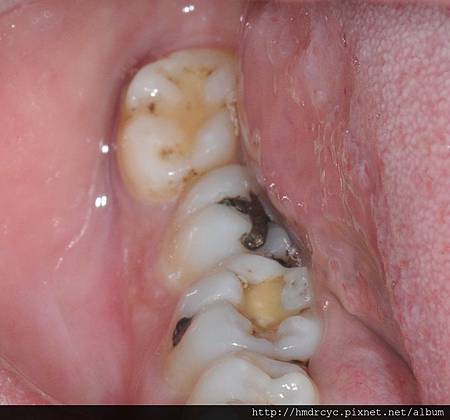

當智齒長歪頂到前面的牙齒

細菌跑進來的時候會無法清潔

頂到前面牙齒的地方會蛀牙

而牙肉包住的地方會牙肉發炎牙周病

如果為了留下一顆沒用的牙齒

卻會害最重要的牙齒蛀牙牙周病

真的要拔除時

可能兩顆都已經壞掉